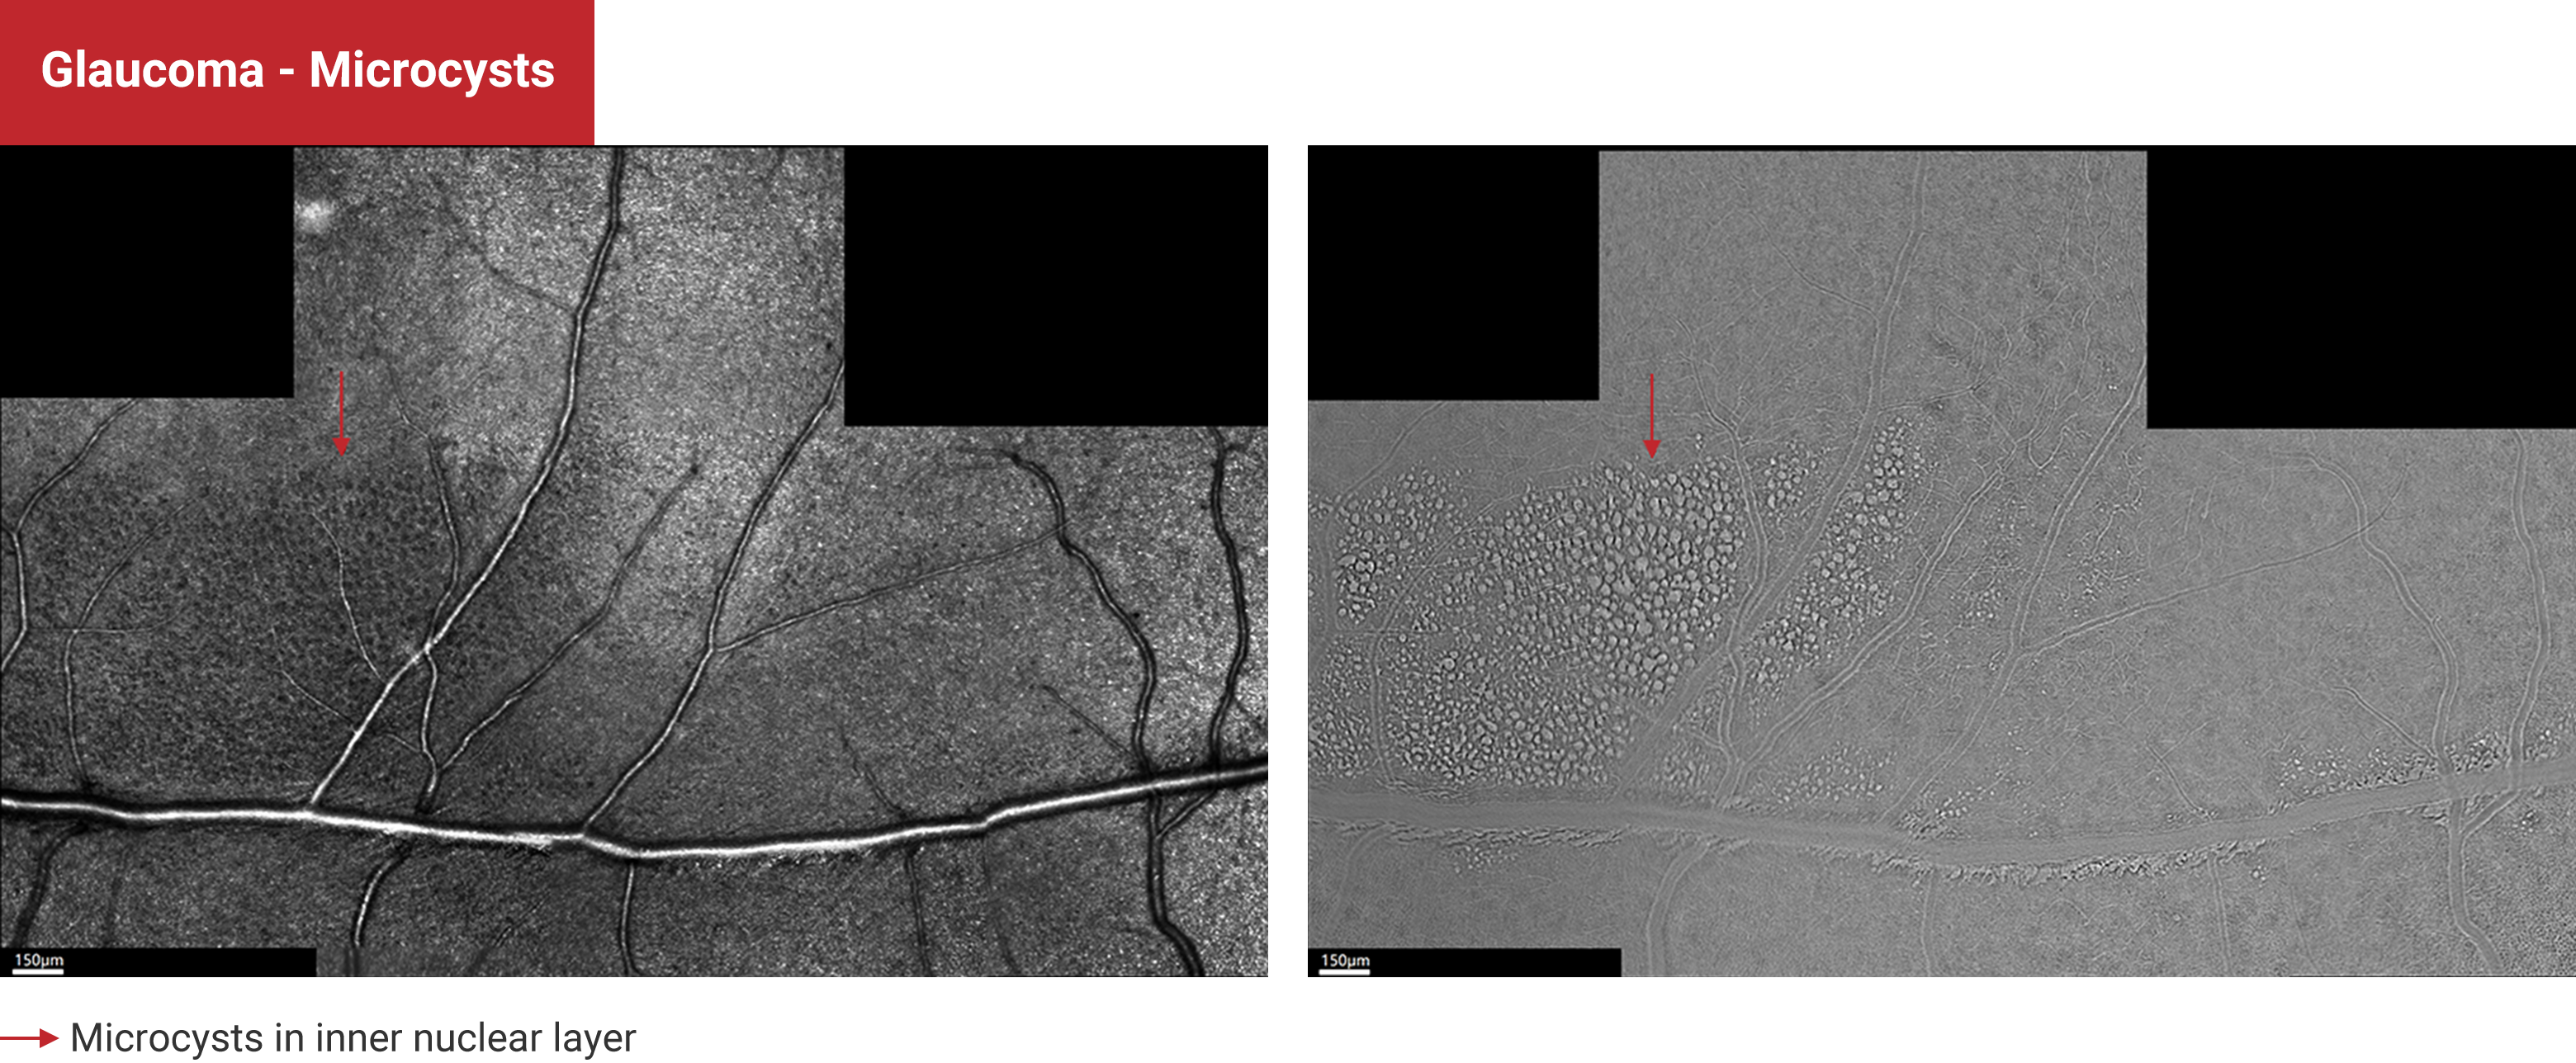

Glaucoma - Microsysts